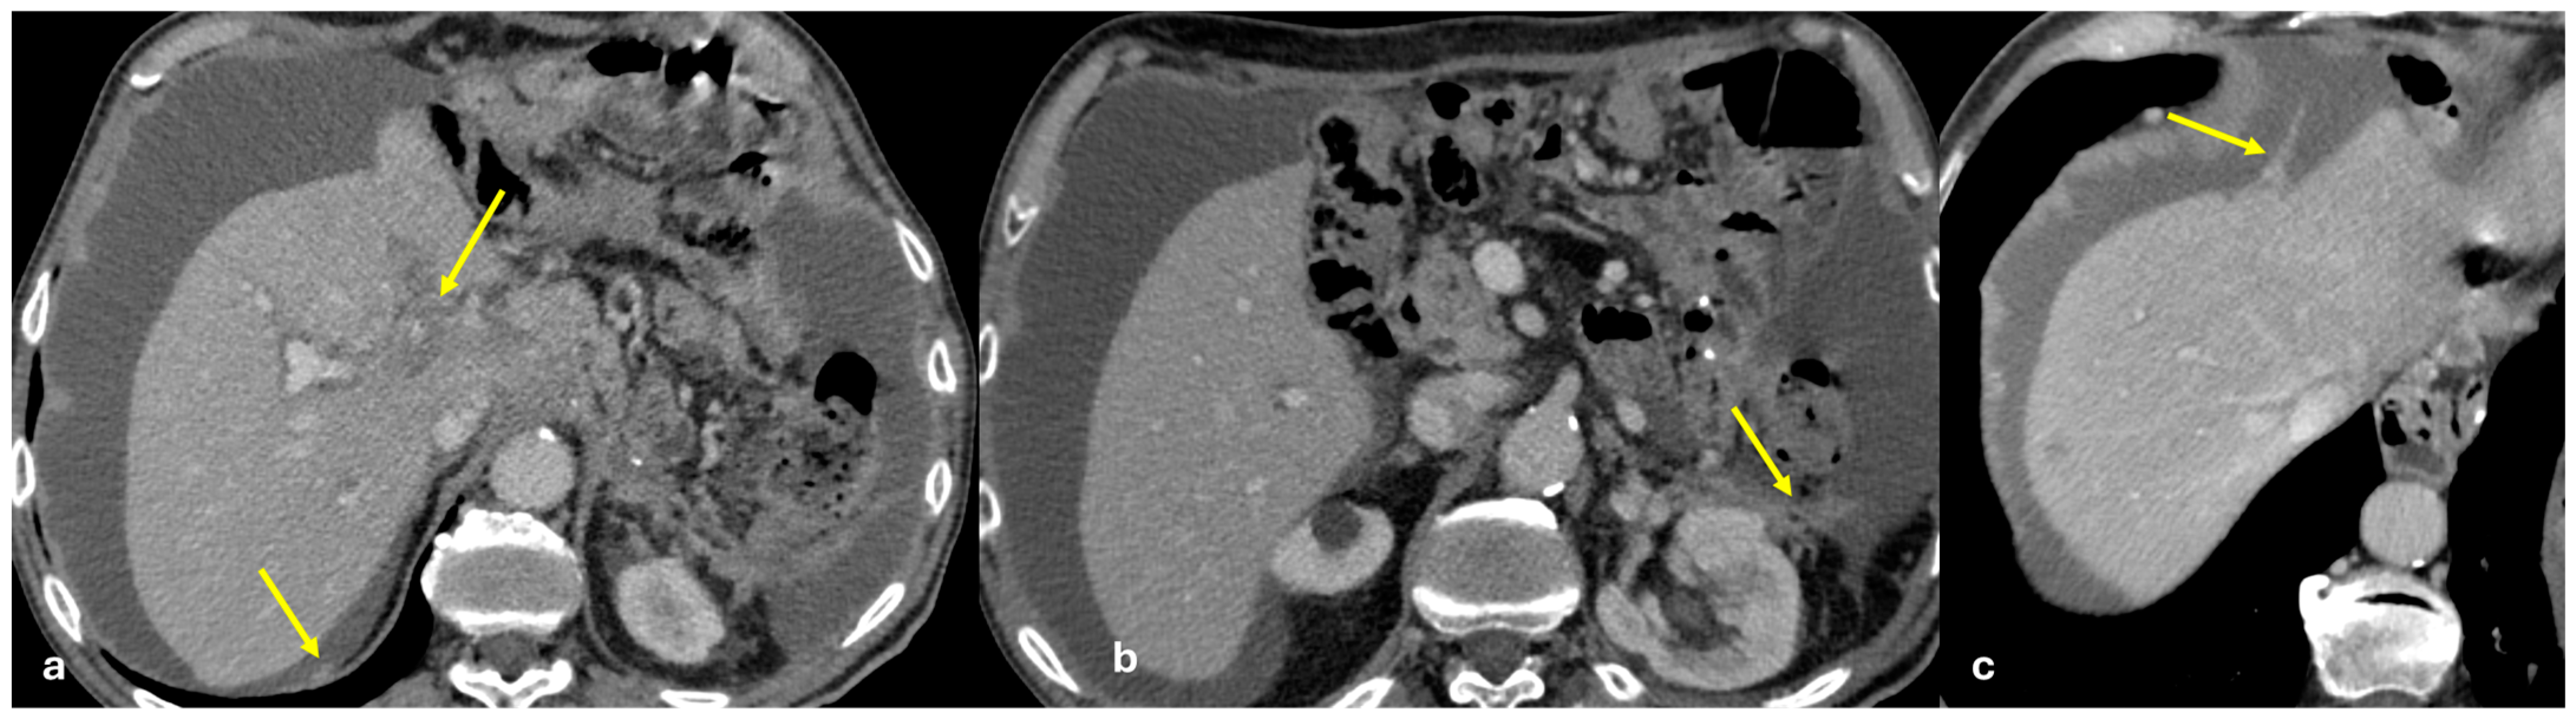

- Micro-nodular pattern: micro-nodules with a diameter ≤ 5 mm (Figure 1);